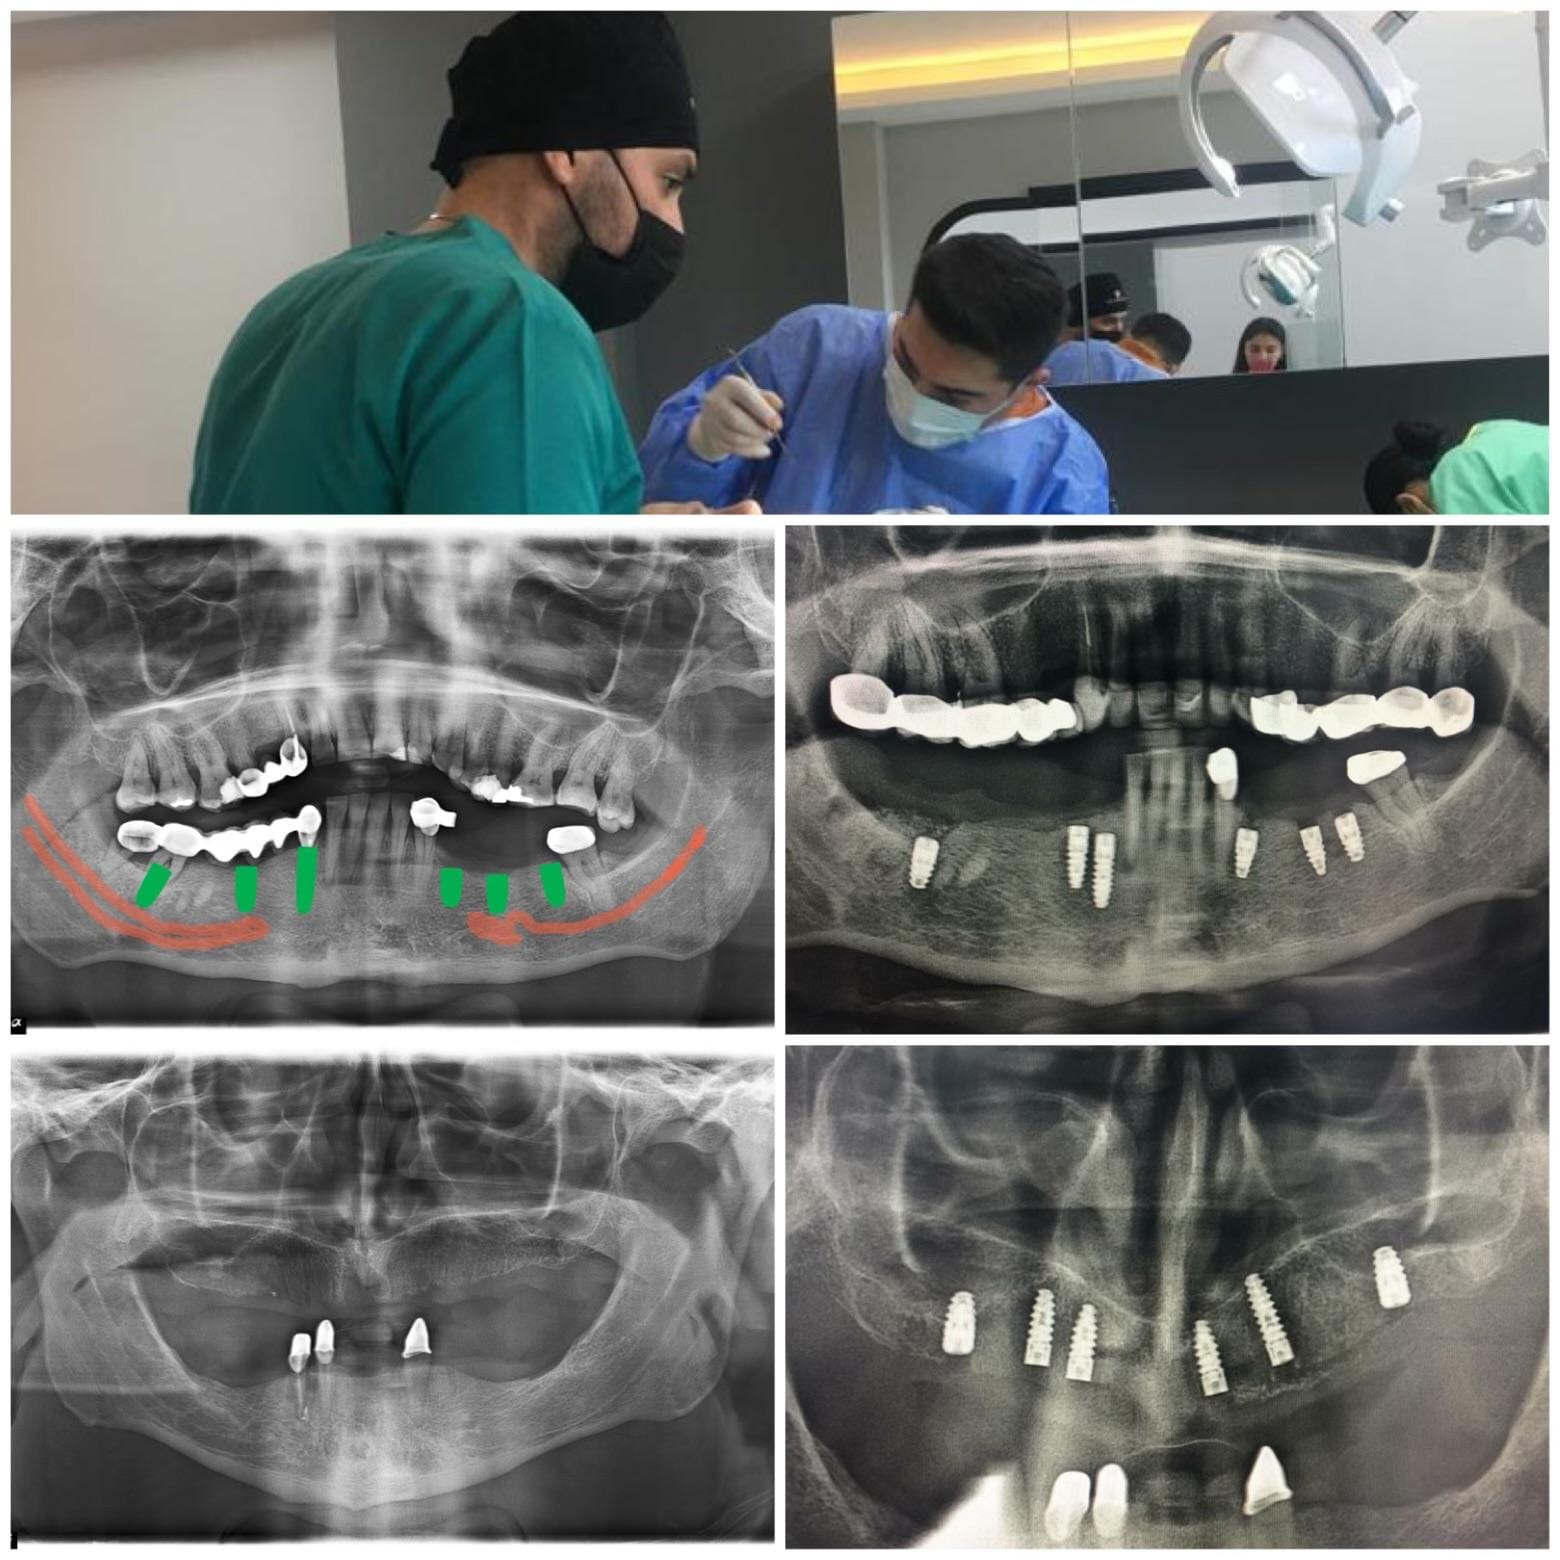

İzmir diş röntgeni hizmetimiz ile ağız ve çene yapısının tüm detaylarını sadece 10 saniyede görüntüleyebilirsiniz. Dijital diş radyografisi teknolojimiz sayesinde çekim sonrası görüntüler anında bilgisayara aktarılır ve hekim tarafından değerlendirilir. Bu sayede tanı ve tedavi süreci hem daha hızlı hem de daha güvenli ilerler.

Panoramik ve 3D radyografi sistemleriyle her hastanın ihtiyacına özel çekimler yapılır. Bu yöntem özellikle implant, ortodonti and kanal tedavisi planlamasında büyük kolaylık sağlar.

HBADent’te kullandığımız panoramik ve 3D diş röntgeni sistemleri, çene kemiği ve diş yapılarının en ince ayrıntılarını dijital ortamda görüntüler. Bu sayede dijital diş radyografisi süreci hem yüksek çözünürlükte hem de düşük radyasyon dozu ile gerçekleşir.

• 3D CBCT (Konik Işınlı Bilgisayarlı Tomografi) teknolojisi

• Kemik yoğunluğu ve sinir hattı analizi

• İmplant planlamasında milimetrik doğruluk

• Hızlı çekim, anında değerlendirme ve yüksek hasta konforu

Bu ileri teknoloji sayesinde İzmir diş röntgeni hizmetimizde hem daha net tanı konur hem de gereksiz tekrar çekimlerin önüne geçilir. HBADent Urla’da modern cihazlarla güvenli ve konforlu görüntüleme deneyimi sunuyoruz.